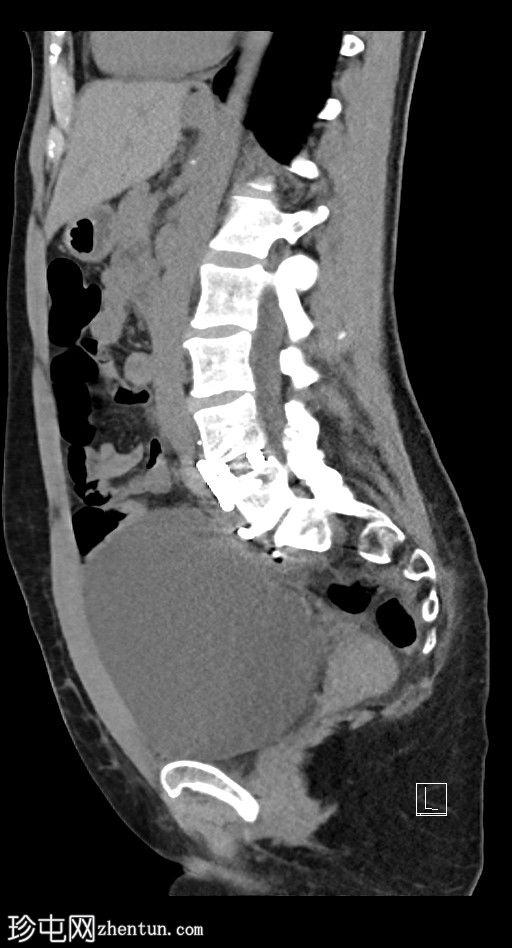

3.jpg

矢状位

平扫

左侧腹膜后可见一巨大囊性肿块,位于左侧腰大肌内侧,紧邻多个手术夹(ALIF手术所用),这些手术夹紧贴囊性肿块后壁。

膀胱已行引流管减压,并被囊性肿块向右侧推移。

子宫和左侧附件在囊性肿块前方保持正常的脂肪间隙,因此附件囊性病变的可能性较小。

左侧输尿管难以辨认,因为它位于囊性肿块下缘后方。